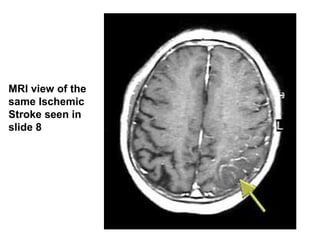

MRI view of the

same Ischemic

Stroke seen in

slide 8

MRI view ofthe same Ischemic Stroke seen in slide 8